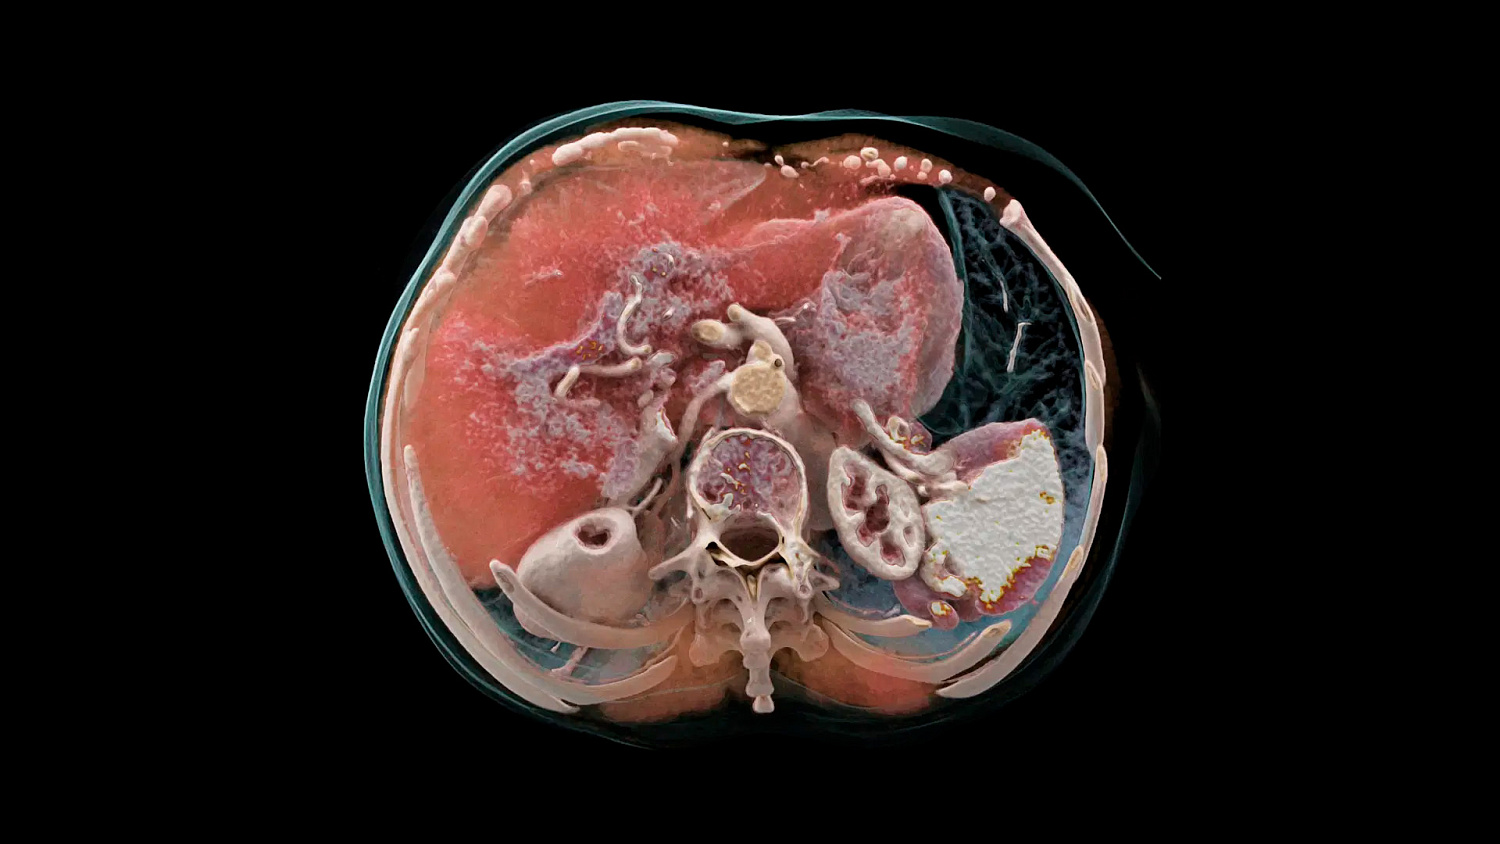

Квантовая спектральная визуализация

Получайте спектральные карты при каждом сканировании, независимо от скорости сканирования, поля обзора или пространственного разрешения. Это обеспечивает точную функциональную оценку без каких-либо компромиссов.

Обеспечьте оптимальное качество изображения и снижение уровня шума с помощью итеративной реконструкции спектральных данных на основе моделей с полной синхронизацией между потоками данных и с высокой и низкой энергией.